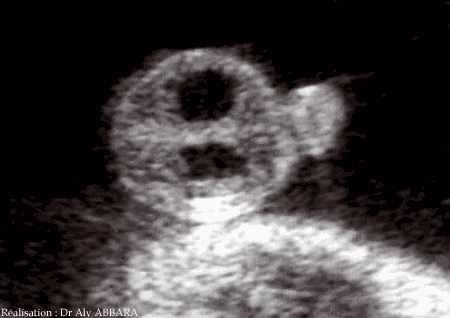

Sexe masculin ; hydrocèle minime à 30 SA